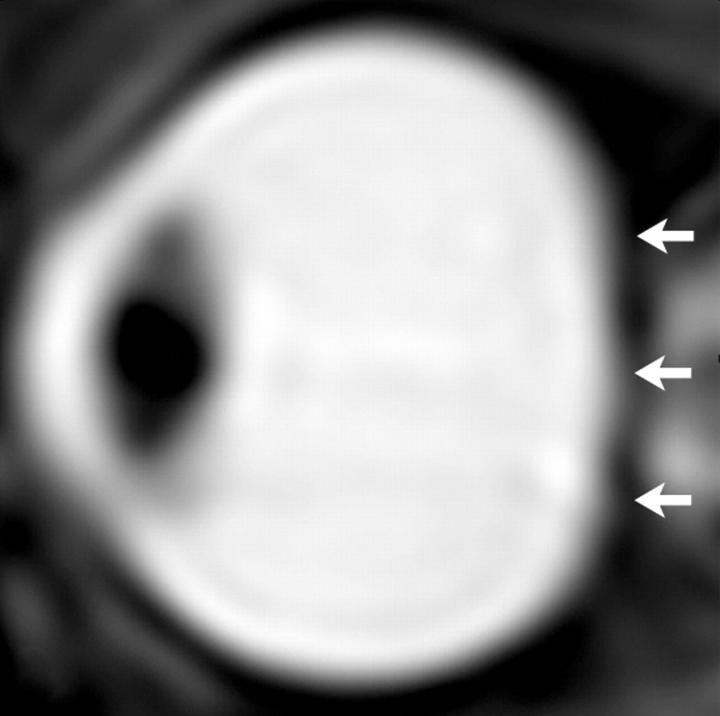

To learn more about the role of CSF in spaceflight-induced visual impairment and eye changes, Dr. Alperin and colleagues performed high-resolution orbit and brain MRI scans before and shortly after spaceflights for seven long-duration mission ISS astronauts.

They compared results with those from nine short-duration mission space shuttle astronauts. Using advanced quantitative imaging algorithms, the researchers looked for any correlation between changes in CSF volumes and the structures of the visual system.

The results showed that, compared to short-duration astronauts, long-duration astronauts had significantly increased post-flight flattening of their eyeballs and increased optic nerve protrusion. Long-duration astronauts also had significantly greater post-flight increases in orbital CSF volume, or the CSF around the optic nerves within the bony cavity of the skull that holds the eye, and ventricular CSF volume--volume in the cavities of the brain where CSF is produced. The large post-spaceflight ocular changes observed in ISS crew members were associated with greater increases in intraorbital and intracranial CSF volume.